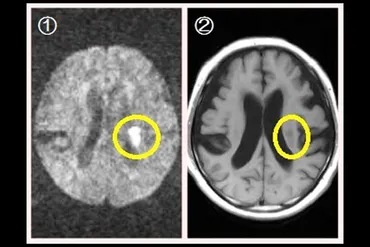

✅ 脳梗塞の検査には、出血の有無を迅速に確認できるCT検査と、発症早期の脳梗塞を描出できるMRI検査があります。

TIAや顔面症状といった初期のサインを見逃さず、早期にMRIなどの検査を受けることで、脳梗塞を早期に発見し、適切な治療を開始することが重要です。